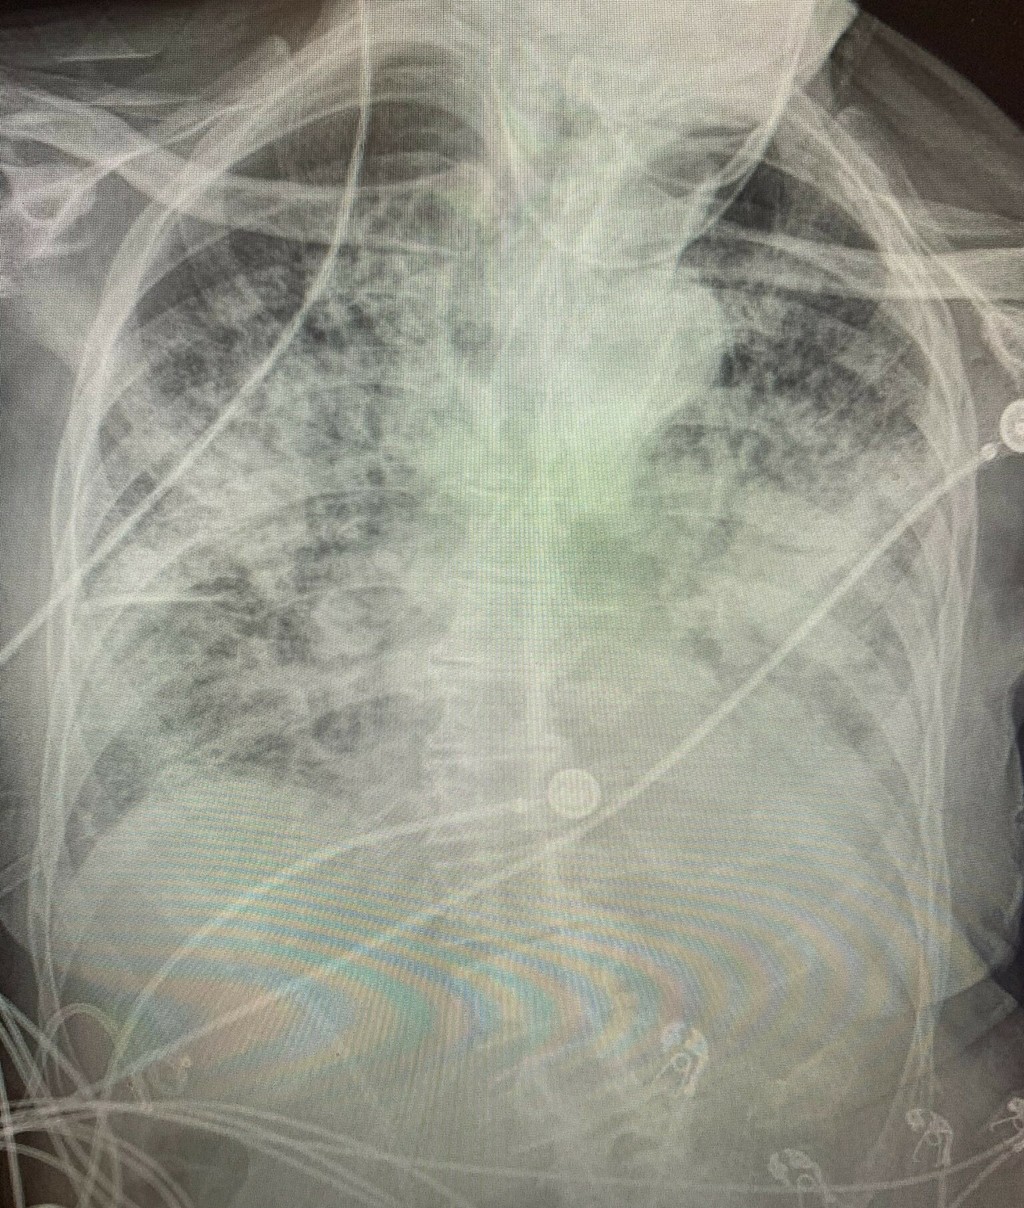

Na röntgenových snímkach sú pľúca po ťažkom priebehu ochorenia COVID-19 silno poškodené aj s jazvami.

Doktorka Brittany Bankhead-Kendallová ošetrovala už tisícky pacientov s koronavírusom. Podľa jej zistení sú röntgenové snímky pľúc fajčiarov trocha zahmlené, ale tie po-covidové sú úplne biele, vykazujú značné zjazvenie a nedostatok vzduchu vstupujúceho do orgánov.

„Po-covidové pľúca sú oveľa zničenejšie, ako akýkoľvek snímok pľúc tuhých fajčiarov, aké som kedy videla," prezradila na Twitteri. „A dýchavičnosť pretrváva a môže sa to zhoršiť," dodala.

Keď sa vzduchové vaky naplnia tekutinou, nie sú schopné prijať toľko kyslíka, ako telo potrebuje. Začína sa to príznakmi ako kašeľ a dýchavičnosť. Na röntgenovej snímke potom pľúcne tkanivo zasiahnuté koronavírusom vyzerá ako z mliečneho skla. Dôsledkom je situácia, keď cez postihnuté tkanivo neprejde kyslík a nenadviaže sa v krvi na hemoglobín. Tým klesá zásobenie tkanív a orgánov tela kyslíkom a človek zomiera.

Doktorka Bankhead-Kendallová uviedla, že všetkým pacientom, u ktorých sa prejavili príznaky ochorenia, urobili röntgen. Až 70-80 percent z nich malo poškodené pľúca.